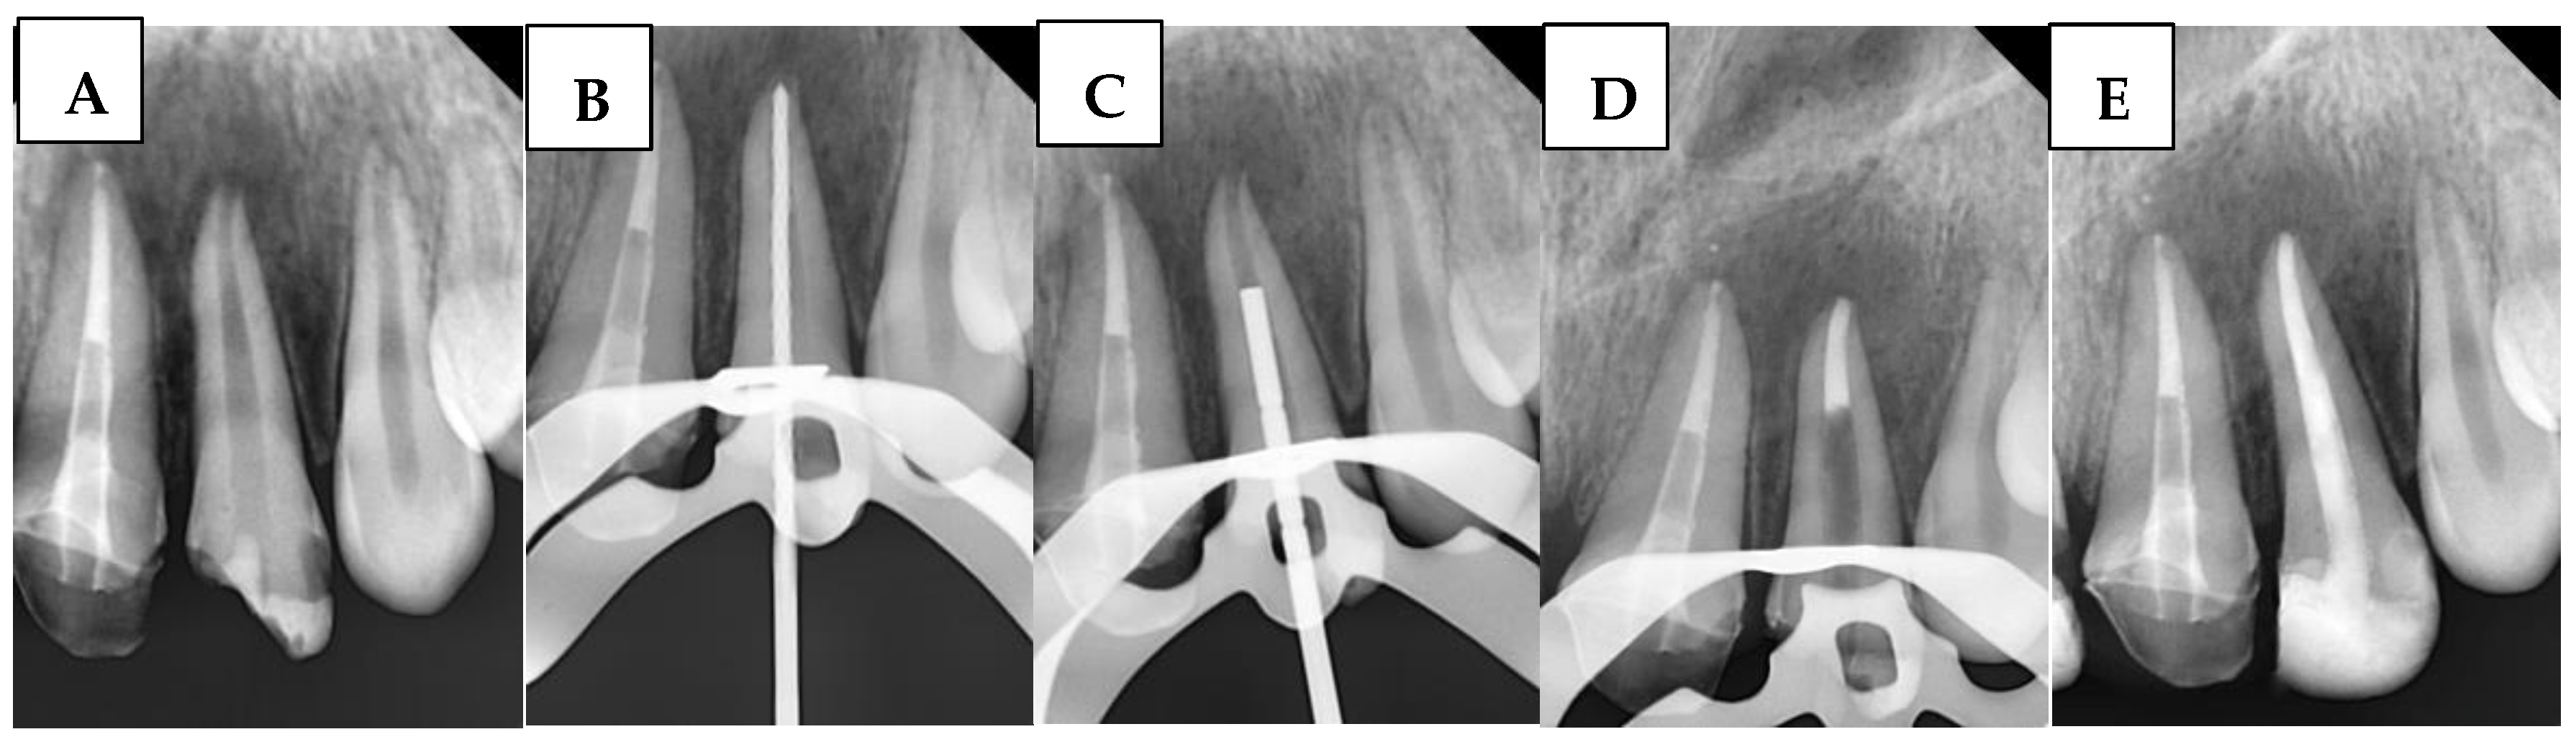

2.6.4. Single Cone Gutta-Percha with BioCeramic Sealer (SBS) Group

A large-sized (#80, taper of 2%) gutta-percha cone (GC) was inserted. The GC was trimmed to fit the canal width as closely as possible without exceeding the WL. The GC was ensured to make tag-back with the apical third of the immature canal and confirmed with a periapical radiograph. Afterward, it was removed, and the immature canal was gently obturated with BS with an adequate amount, and the GC was inserted again, and another apical radiograph was taken to confirm that the canal was properly filled without gaps and voids. Any BioCeramic extrusion was recorded at this stage in the DPF. Figure 3 illustrates the steps of the procedure in the SBS group.

Figure 3. Sequential steps of the procedure in the SBS group: (A) Preoperative periapical radiograph, (B) Working length radiograph, (C) Cone fit, and (D) Postoperative radiograph.